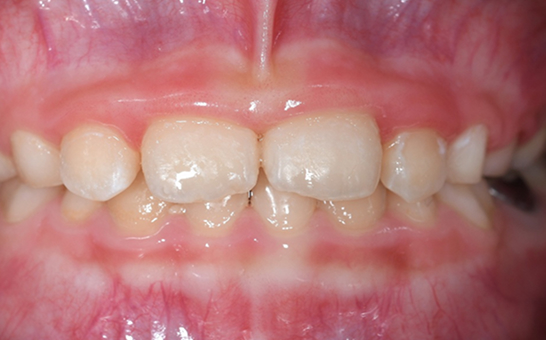

인비절라인 퍼스트(Invisalign First)는 어린이와

성장기 청소년을 위한 투명 교정 장치로, 치아와 턱뼈가

성장하는 과정에 맞춰 설계된 교정 시스템입니다.

해당하는 증상이 있다면 전문의와 상담 후 조기 교정 시

성장기 어린이에게 교합이 틀어지는것을 미리 예방 할 수 있습니다.

※ 바른선택치과의원은 의료법을 준수하며 위 케이스는 실제 내원 환자분의 동의하에 공개된 사진과 동일한 환자분께 같은 조건에서 촬영한 사진을 활용했습니다.

개인에 따라 진료 및 치료 방법이 다르게 적용할 수 있으며, 효과와 부작용이 개인마다 다르게 나타날 수 있는 점을 안내해 드리며, 진료 전 전문의료진과 충분한 상담을 권해드립니다.